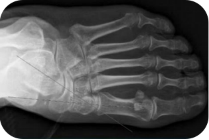

X线测量法:第一跖骨距骨角、距舟覆盖角及跟骨倾斜角等参数的测量,对足进行影像学评估。

足负重前后位、足负重侧位(足内弓角测量、外弓角测量、跟骨倾斜角)。